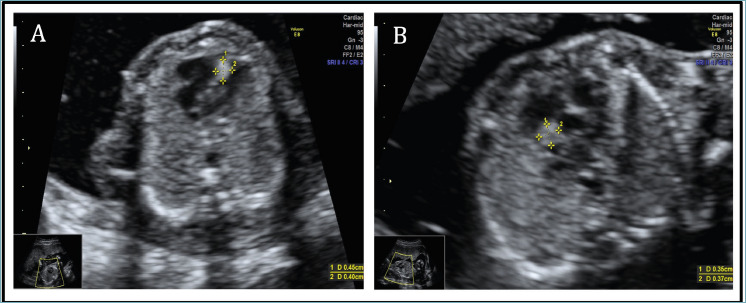

In the present case, ultrasonography at 20+2 gestational weeks identified two echogenic masses suspicious of rhabdomyomas in the foetal heart. Neither of these tumours caused significant haemodynamic instability. Genetic testing of DNA extracted from amniocytes revealed a pathogenic variant of the TSC1 gene, supporting the diagnosis of tuberous sclerosis. The pregnancy was terminated at 21+1 weeks. Pathological examination confirmed the presence of two cardiac rhabdomyomas, histologically characterised by distinctive large vacuolated cells with central nuclei and radial cytoplasmic extensions.